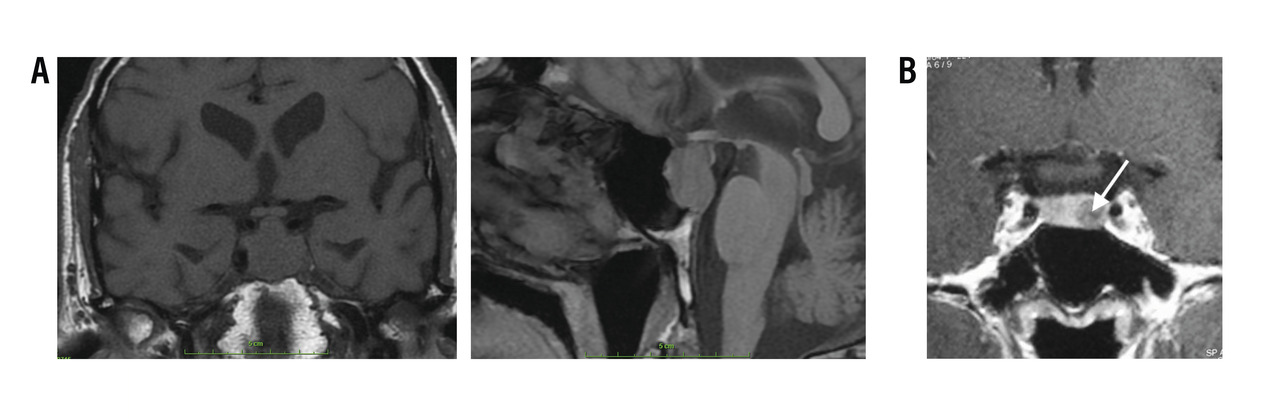

IRM hypophysaire

L’imagerie de référence est l’IRM hypophysaire, en coupe fine, avec injection (rang B).

Les micro-adénomes (< 10 mm) sont intrasellaires, ils apparaissent arrondis, homogènes (rang B), en hypo­signal en T1 et hypo-, iso- ou hypersignal en T2 (rang C). La prise de contraste est homogène, volontiers retardée par rapport au parenchyme sain (fig. 5) [rang C].

Les macro-adénomes (> 10 mm) s’étendent en extrasellaire (rang B), leur signal est iso-T1, et souvent hétérogène en T2, les plages nécrotiques apparaissent en hypersignal T2 (rang C). La prise de contraste est le plus souvent hétéro­gène hypo-intense par rapport à l’hypophyse saine (fig. 5) [rang C].

Diagnostics différentiels en imagerie

Les processus tumoraux intrasellaires les plus fréquents sont le craniopharyngiome et le méningiome.

Le craniopharyngiome apparaît en IRM comme une masse hétérogène, souvent kystique, avec une capsule prenant le contraste (rang C). Les calcifications sont fréquentes et nécessitent de réaliser un scanner en fenêtre osseuse car elles sont très mal visualisées en IRM (rang C).

Les méningiomes sont des lésions qui prennent très fortement le produit de contraste et qui « s’accrochent » à la dure-mère, donnant une image en « queue de comète » (rang C).

Les autres diagnostics différentiels sont la grosse hypophyse de la femme jeune, l’hypophysite auto-­immune, les métastases, la sarcoïdose, l’histiocytose, la tuberculose (rang C).